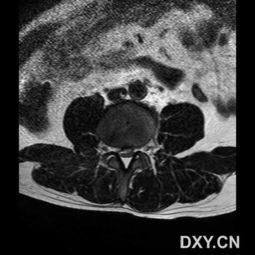

首先,我们来揭开腰椎突出的神秘面纱。腰椎突出,顾名思义,就是腰椎间盘的一部分从正常位置突出,压迫到周围的神经根,导致一系列不适症状。据统计,我国腰椎突出患者人数已超过1亿,而且这个数字还在逐年攀升。

1. 腰痛:这是腰椎突出的最常见症状,疼痛可能局限于腰部,也可能向下放射至臀部、大腿后侧。

2. 下肢疼痛、麻木:当突出的椎间盘压迫到神经根时,会引起下肢疼痛、麻木,甚至无力。